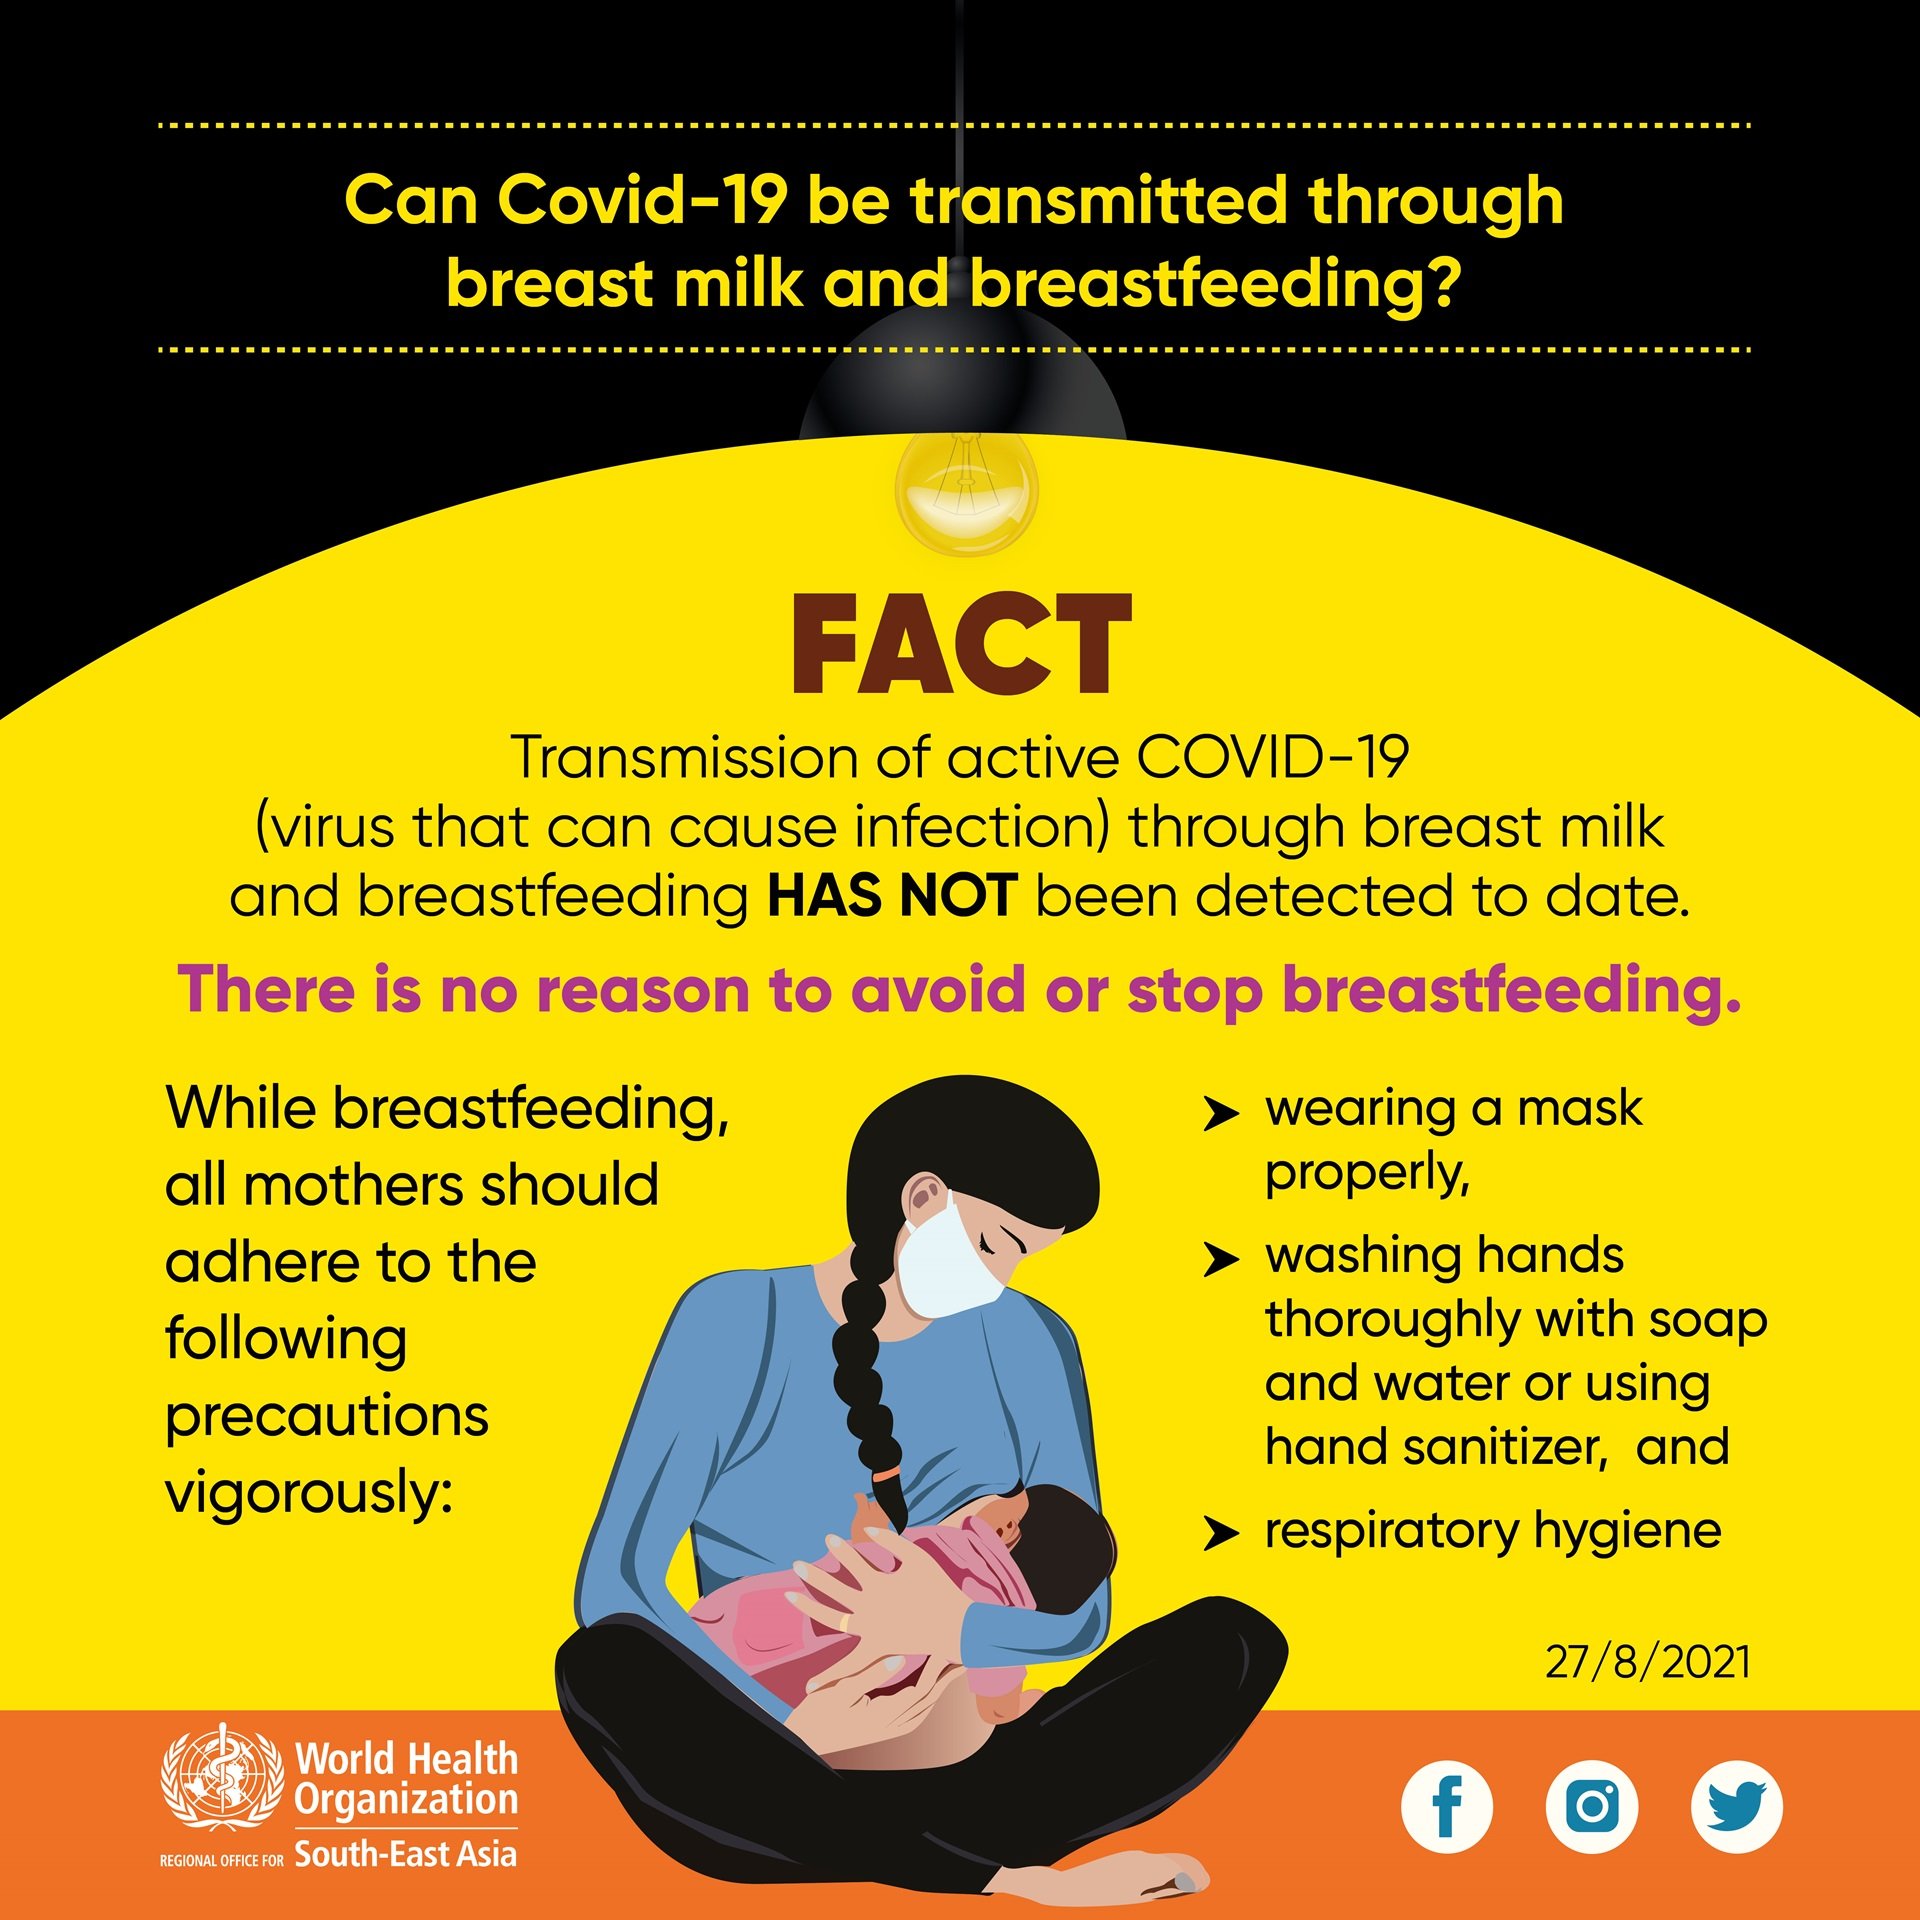

Can COVID-19 be transmitted through breast milk and breastfeeding?

FACT

Transmission of active COVID-19 (virus that can cause infection) through breast milk and breastfeeding HAS NOT been detected to date. There is no reason to avoid or stop breastfeeding.